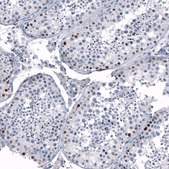

Monoclonal Anti-SALL4 antibody produced in mouse

immunofluorescence: 2-10 μg/mL (ICC-IF), immunohistochemistry: 1:2500 - 1:5000, western blot: 1 μg/mL

The Human Protein Atlas project can be subdivided into three efforts: Human Tissue Atlas, Cancer Atlas, and Human Cell Atlas. The antibodies that have been generated in support of the Tissue and Cancer Atlas projects have been tested by immunohistochemistry against hundreds of normal and disease tissues and through the recent efforts of the Human Cell Atlas project, many have been characterized by immunofluorescence to map the human proteome not only at the tissue level but now at the subcellular level. These images and the collection of this vast data set can be viewed on the Human Protein Atlas (HPA) site by clicking on the Image Gallery link. We also provide Prestige Antibodies® protocols and other useful information.

• IHC tissue array of 44 normal human tissues and 20 of the most common cancer type tissues.